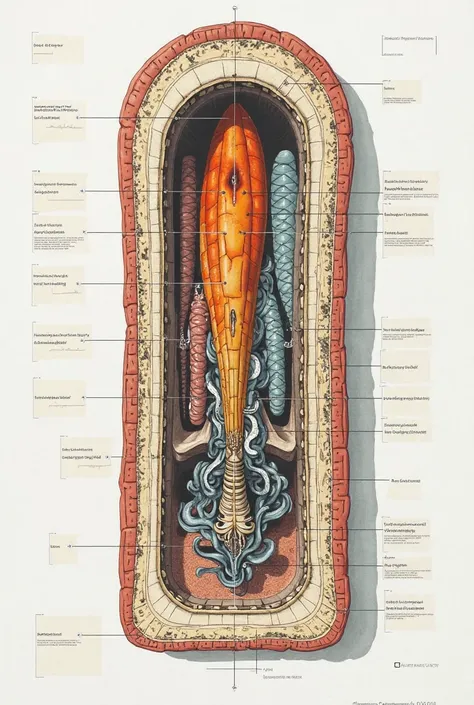

A diagram of the anatomy of the human body

Realice un dibujo de la piel. Coloque las siguientes referencias: Epidermis Fermis Hypodermis Keratinized squamous stratified epithelium Hair Sebaceous gland Sweat gland Pilo erector muscle Connective tissue Blood vessels Nerves Adipocytes

Epidermis Fermis Hypodermis Keratinized squamous stratified epithelium Hair Sebaceous gland Sweat gland Pilo erector muscle Connective tissue Blood vessels Nerves Adipocytes